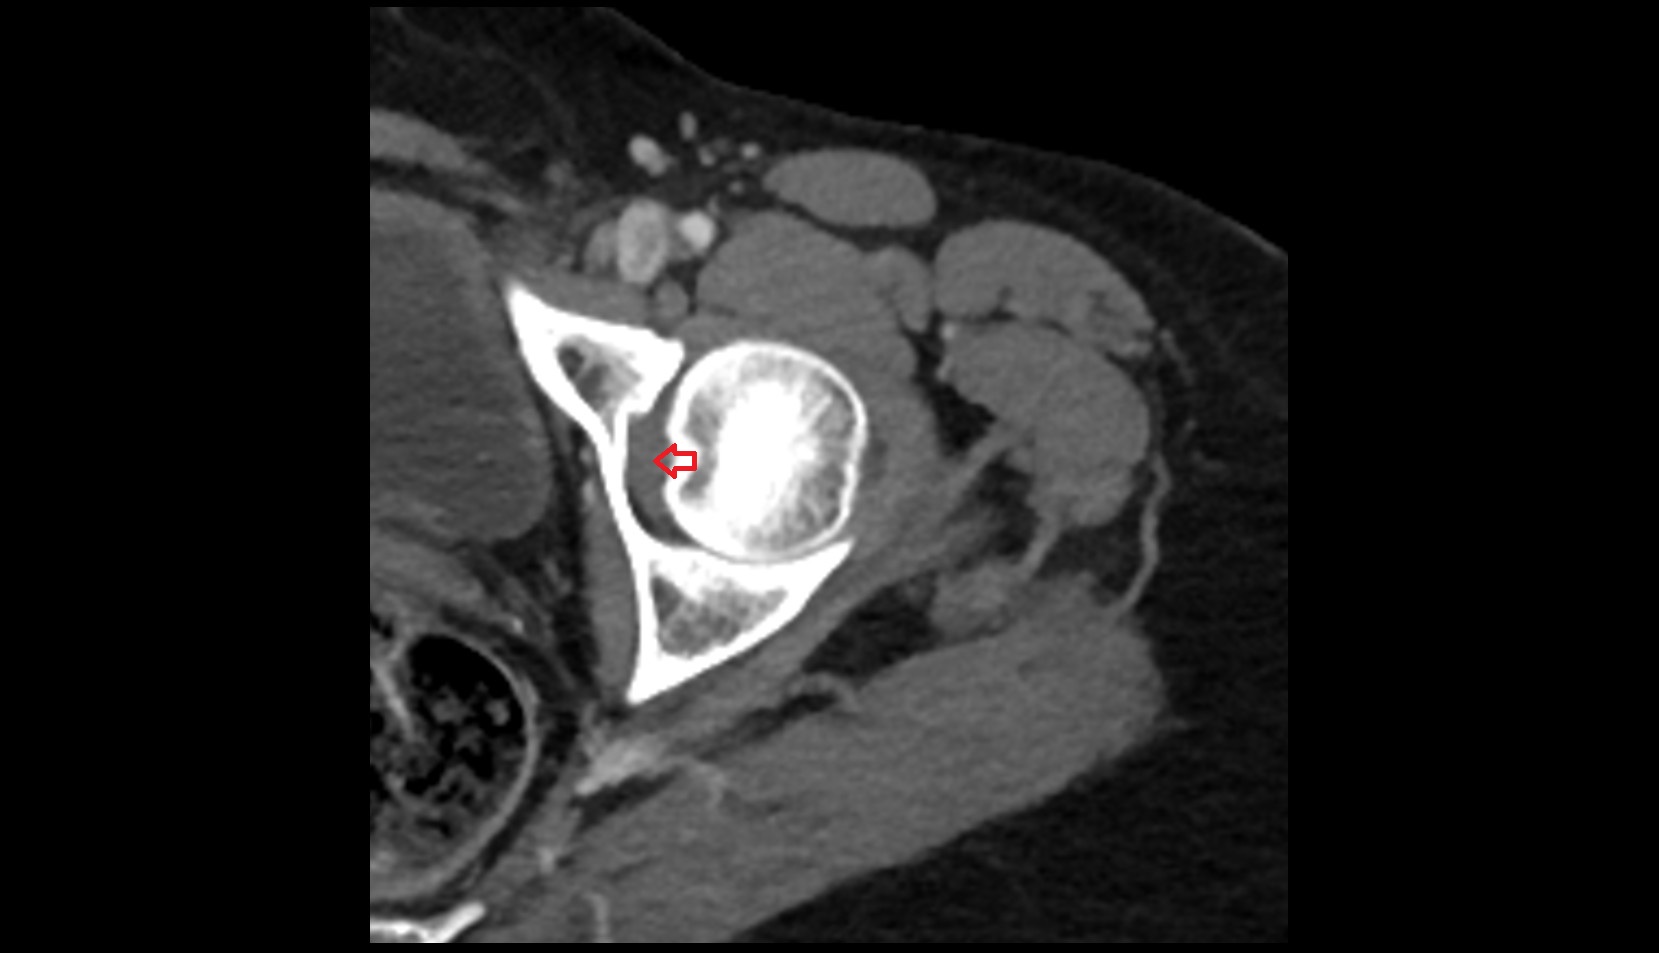

- Hip joint